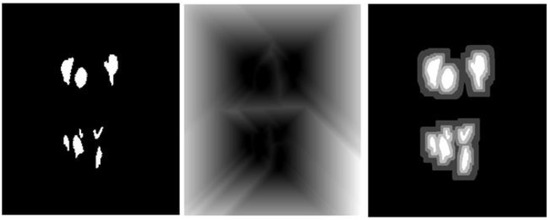

Appendix B.1. Multi-Level Distance Features